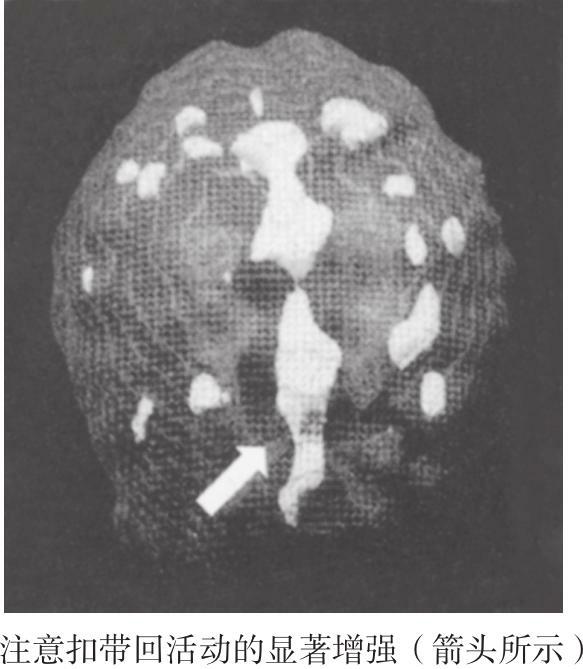

图1-4 贝齐过分注意的大脑顶-底面3D成像图

因为已经有了长达9个月的婚姻咨询经验,所以当我看到他们大脑成像结果的时候,就立刻想到了结果的临床意义(见图1-4)。实际上,我因为自己没早点儿想到给他们做脑成像检查而有点儿生气。从成像结果上看,贝齐的扣带回表现出了非常明显的过度激活,这导致她的注意力转移存在一定的障碍,而这种注意力转移上的障碍会导致她总是固执地执着于某一件事情或某一个想法。她的大脑激活模式决定了她总是反复纠结同一件事情,而鲍勃的激活结果则完全不同。在静息状态下,他的大脑表现得很正常,而当他开始集中注意力的时候,大脑的额叶部分却完全没有激活反应(见图1-5)。可是,在人们集中注意力的时候,额叶区域的激活程度应该变强。所以他在注意力集中上存在问题,也很难把注意力放到贝齐身上,或者说,他越是想关注贝齐,反而越没法把注意力集中到贝齐身上。他只能用反其道而行之的方法来让自己的大脑工作起来。鲍勃行为上的症状和他的大脑成像结果很明显地说明,他和他的孩子们一样都患有注意力缺陷障碍。这一点儿都不奇怪,因为注意力缺陷障碍往往是遗传性的。